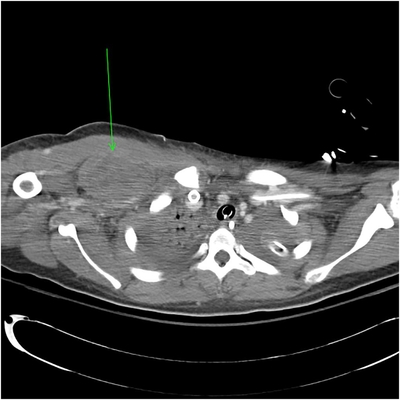

Click on an image below to view more info.